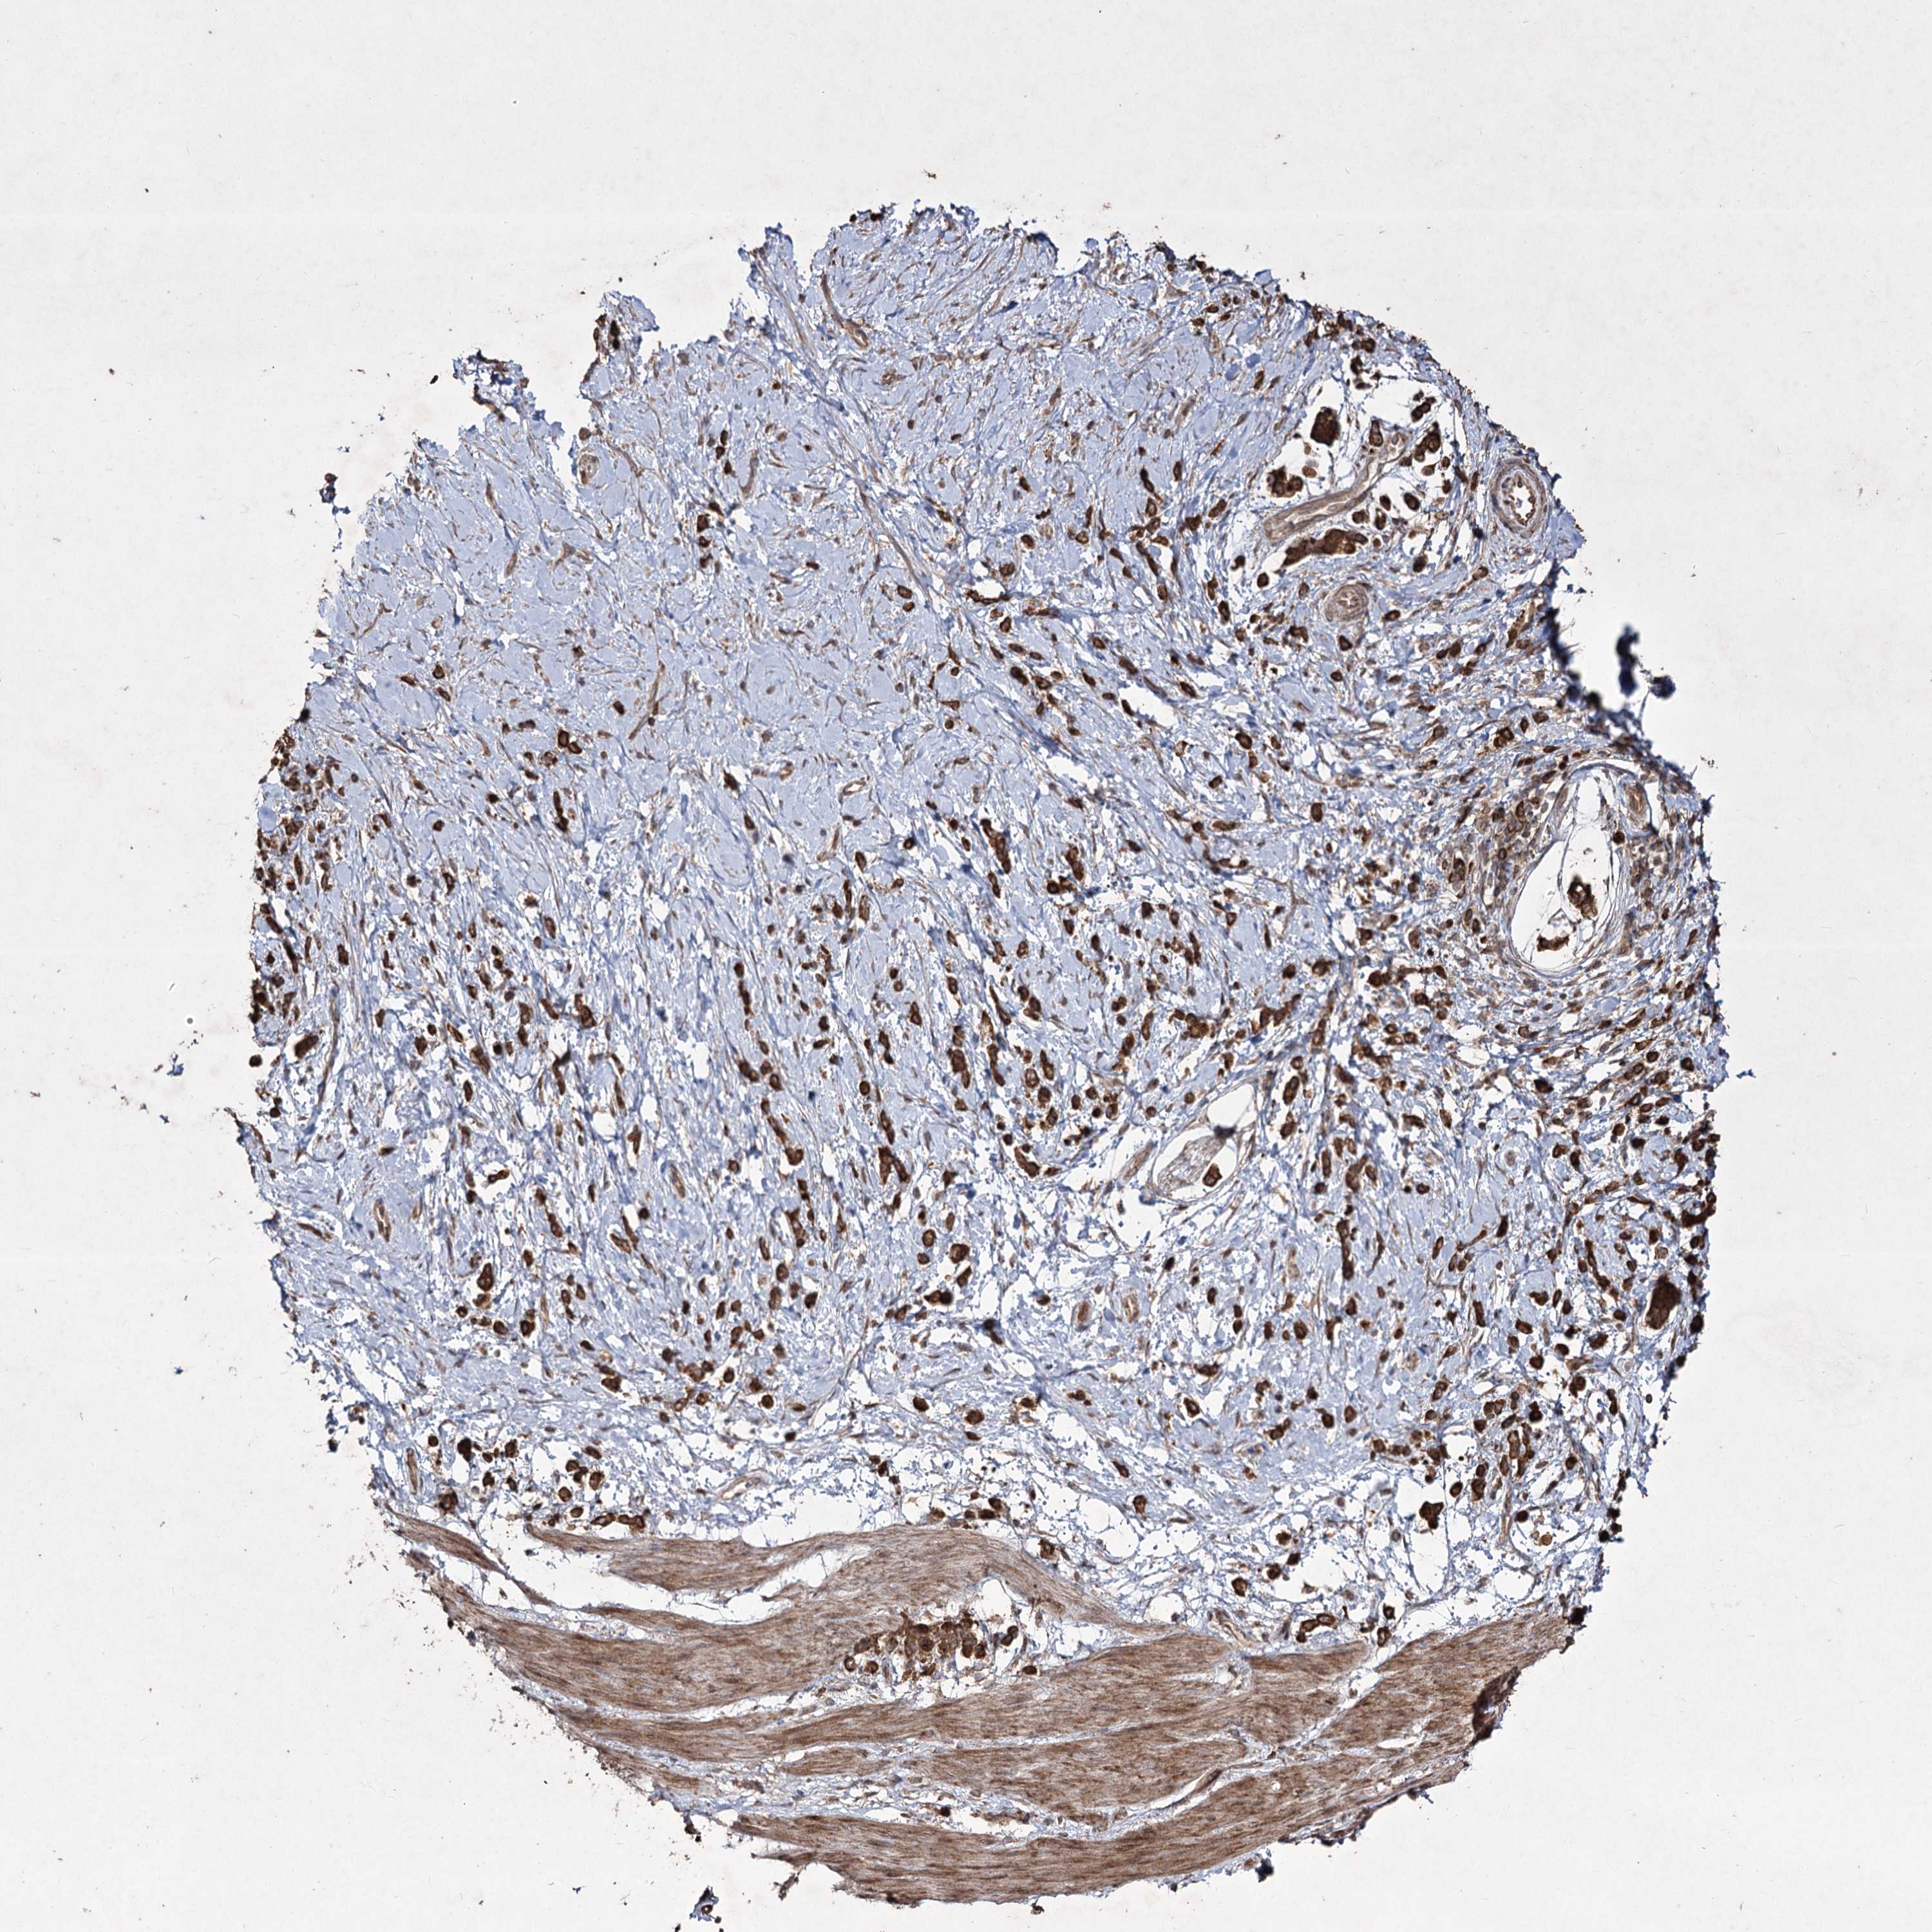

STOMACH CANCER - Protein expressioni

A mouse-over function shows sample information and annotation data. Click on an image to view it in a full screen mode. Samples can be filtered based on level of antibody staining by selecting one or several of the following categories: high, medium, low and not detected. The assay and annotation is described here.

Antibody stainingi

Antibody staining in the annotated cell types in the current human tissue is reported as not detected, low, medium, or high, based on conventional immunohistochemistry profiling in selected tissues. This score is based on the combination of the staining intensity and fraction of stained cells.

Each image is clickable and will lead to virtual microscopy that enables deeper exploration of all samples and also displays staining intensity scores, fraction scores and subcellular localization as well as patient and tissue information for each sample.

Staining

High

Medium

Low

Not detected

Intensity

Strong

Moderate

Weak

Negative

Quantity

>75%

75%-25%

<25%

None

Location

Nuclear

Cytoplasmic/membranous

Cytoplasmic/membranous,nuclear

Adenocarcinoma, NOS

Adenocarcinoma, High grade